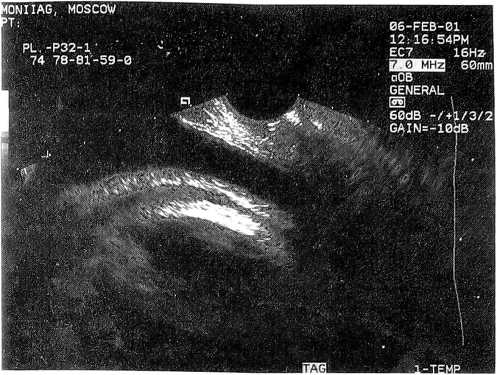

Мы располагаем случаями самопроизвольных родов при равномерной толщине рубца 3-4 мм (рис. 1) с хорошей его васкуляризацией. Кстати, такова толщина и интактного нижнего сегмента матки в конце беременности и в родах. Рубец же, где имеются локальные истончения, независимо от его общей толщины (рис. 2), по нашему мнению, является неполноценным.

Рис. 1. Состоятельный (преимущественно мышечный, равномерной толщины) рубец на матке